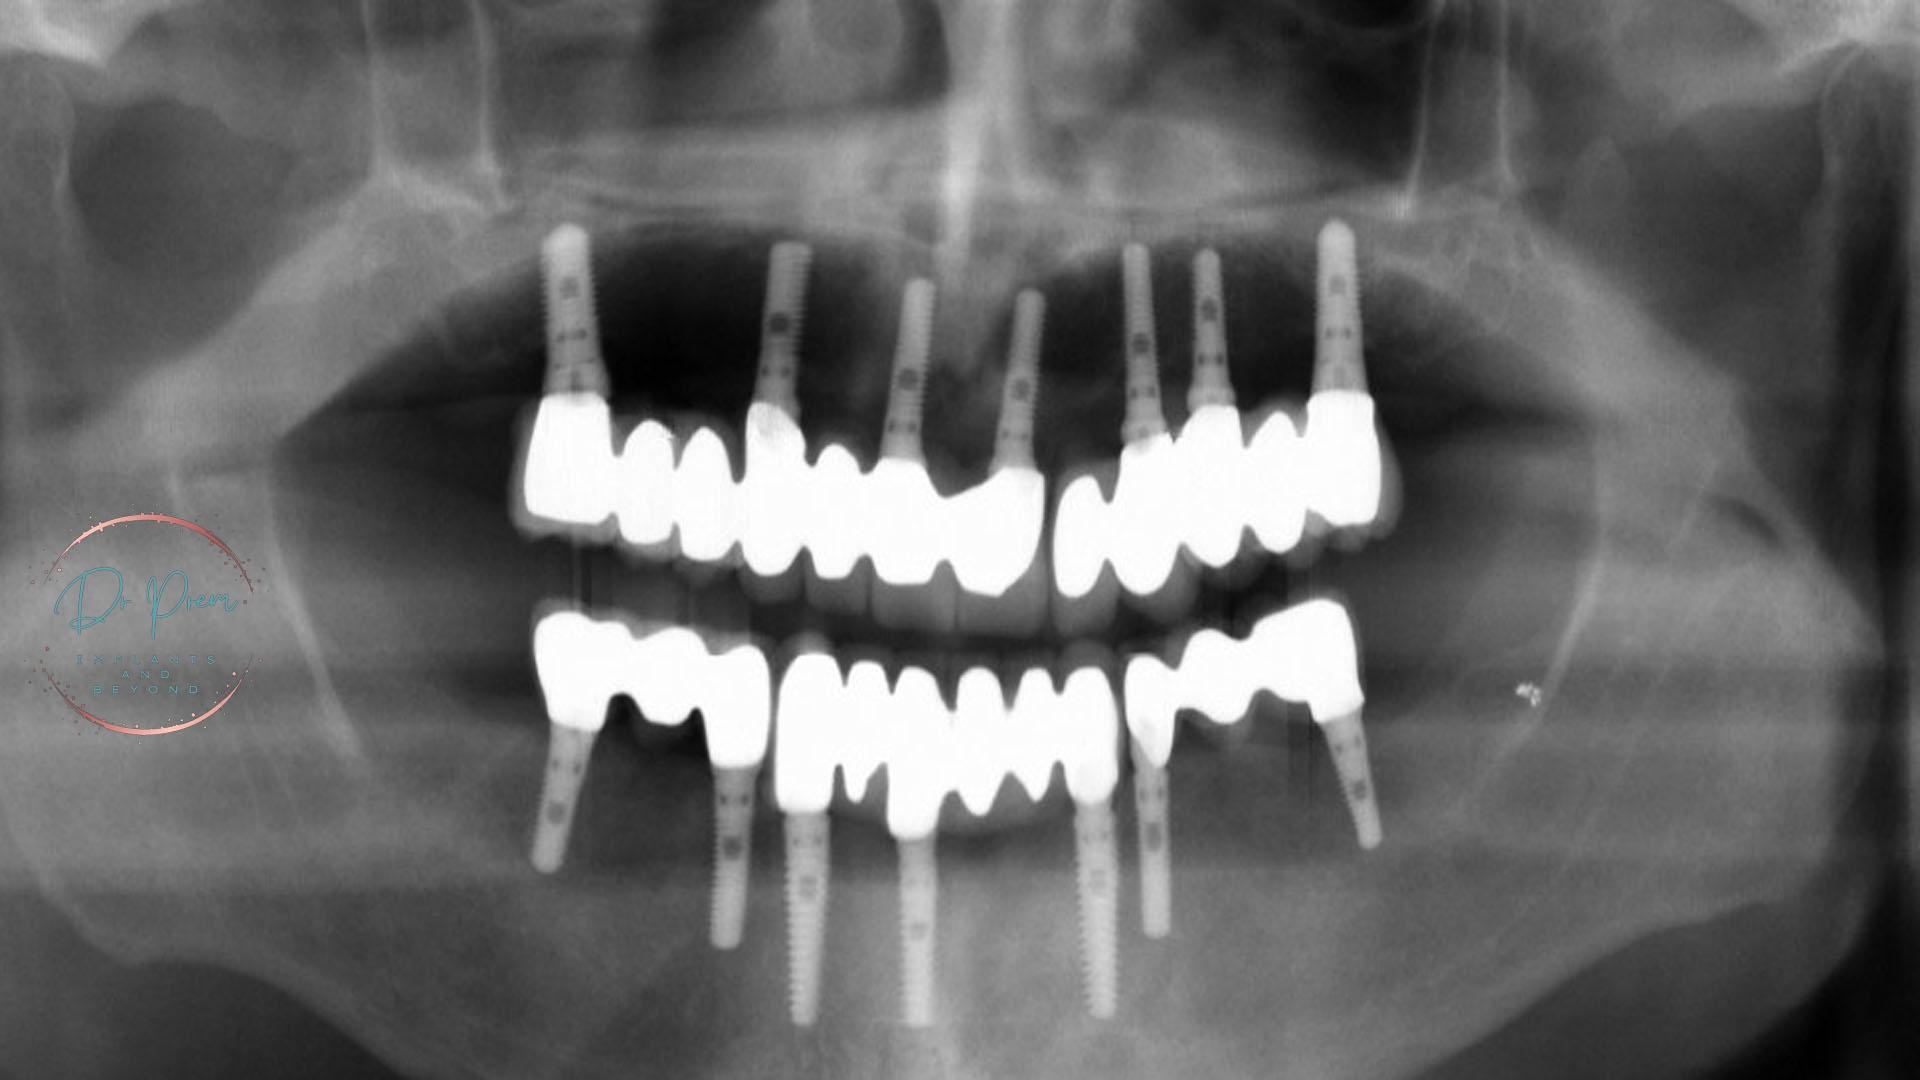

We offer a range of customized solutions, including dental bonding, veneers, and orthodontic treatments, to address teeth gaps and create a seamless, natural-looking smile.